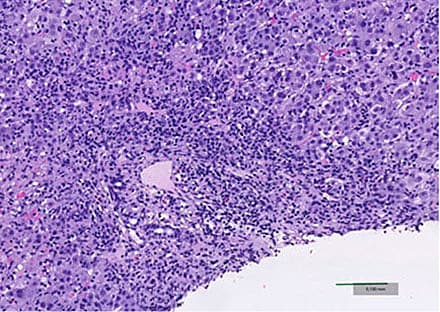

eller negativ. Leverbiopsi fra fem af patienterne viste inflammatoriske forandringer, som var forenelige med såvel AIH som toksisk hepatitis.